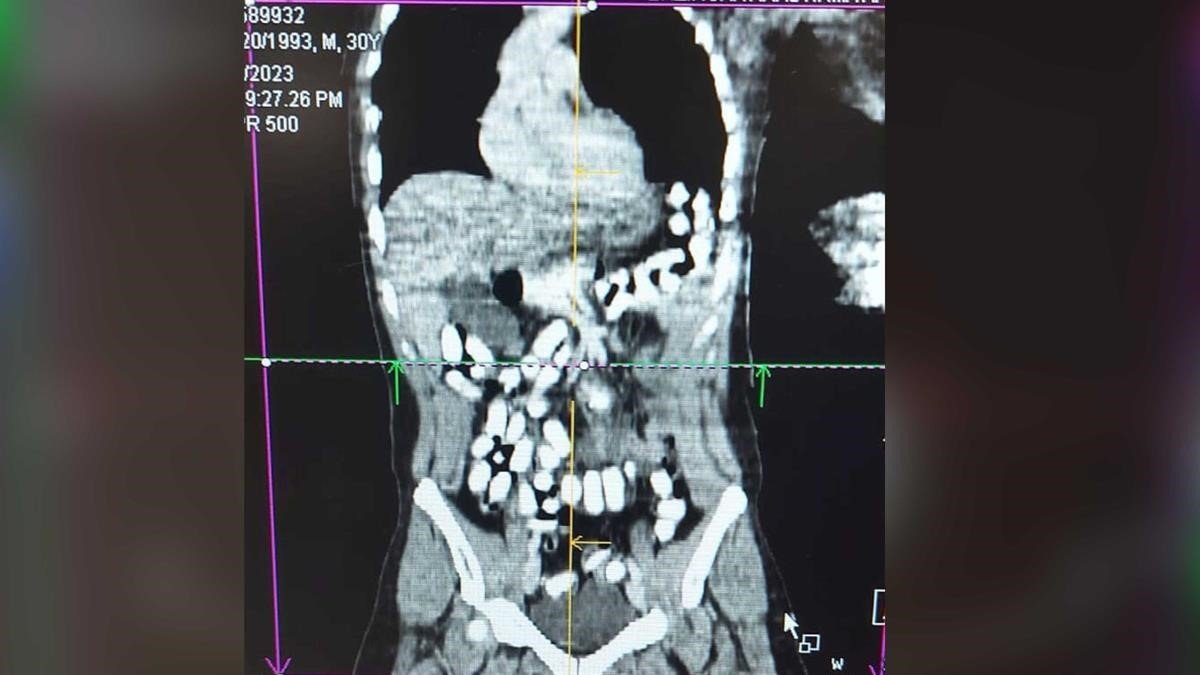

İl Emniyet Müdürlüğü Narkotik Suçlarla Mücadele Şube Müdürlüğü ile Kaçakçılık ve Organize Suçlarla Mücadele Şube Müdürlüğü ve İstihbarat Şube Müdürlüğü ekiplerince yapılan ortak çalışmada; Uygulama noktasında durdurulan, yolcu otobüsünde yolcu olarak bulunan A.A isimli şahsa alınan iç beden muayenesi kararına istinaden hekim gözetiminde çekilen "tomografi" neticesinde mide ve bağırsak kısmında uyuşturucu madde olabileceği değerlendirilen yabancı maddeler tespit edildi. Şahıs Mengücek Gazi Eğitim ve Araştırma Hastanesinde müşahede altına alınarak midesinden 70 adet kapsül halinde daralı ağırlığı ise 499,23 gr Afyon sakızı maddesi ele geçirildi.